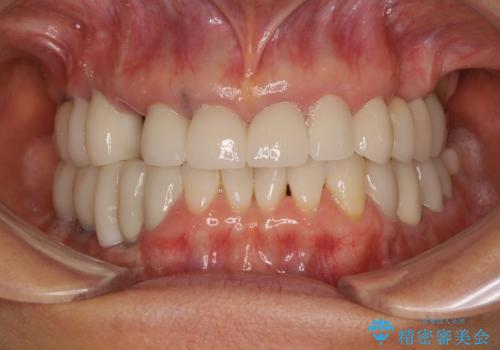

全顎的な治療後に、急遽ニューヨークへ転居されることとなったのですが、治療後から経過観察を行っていた右上犬歯が歯肉縁下に及ぶむし歯のため、クラウンが土台ごと外れてしまったとの連絡がありました。

他の部位にインプラント治療を行っていたことから、こちらの歯に対してもインプラントによる補綴治療を希望されたため、1泊での帰国時に抜歯、インプラント埋入、仮歯の装着を行い、数ヶ月後の帰国時にオールセラミッククラウンの型取りと装着を行う計画としました。

インプラント埋入時は1泊、補綴治療時には3週間ほど日本に滞在していただき、2回の渡航で無事に治療を終えることができました。